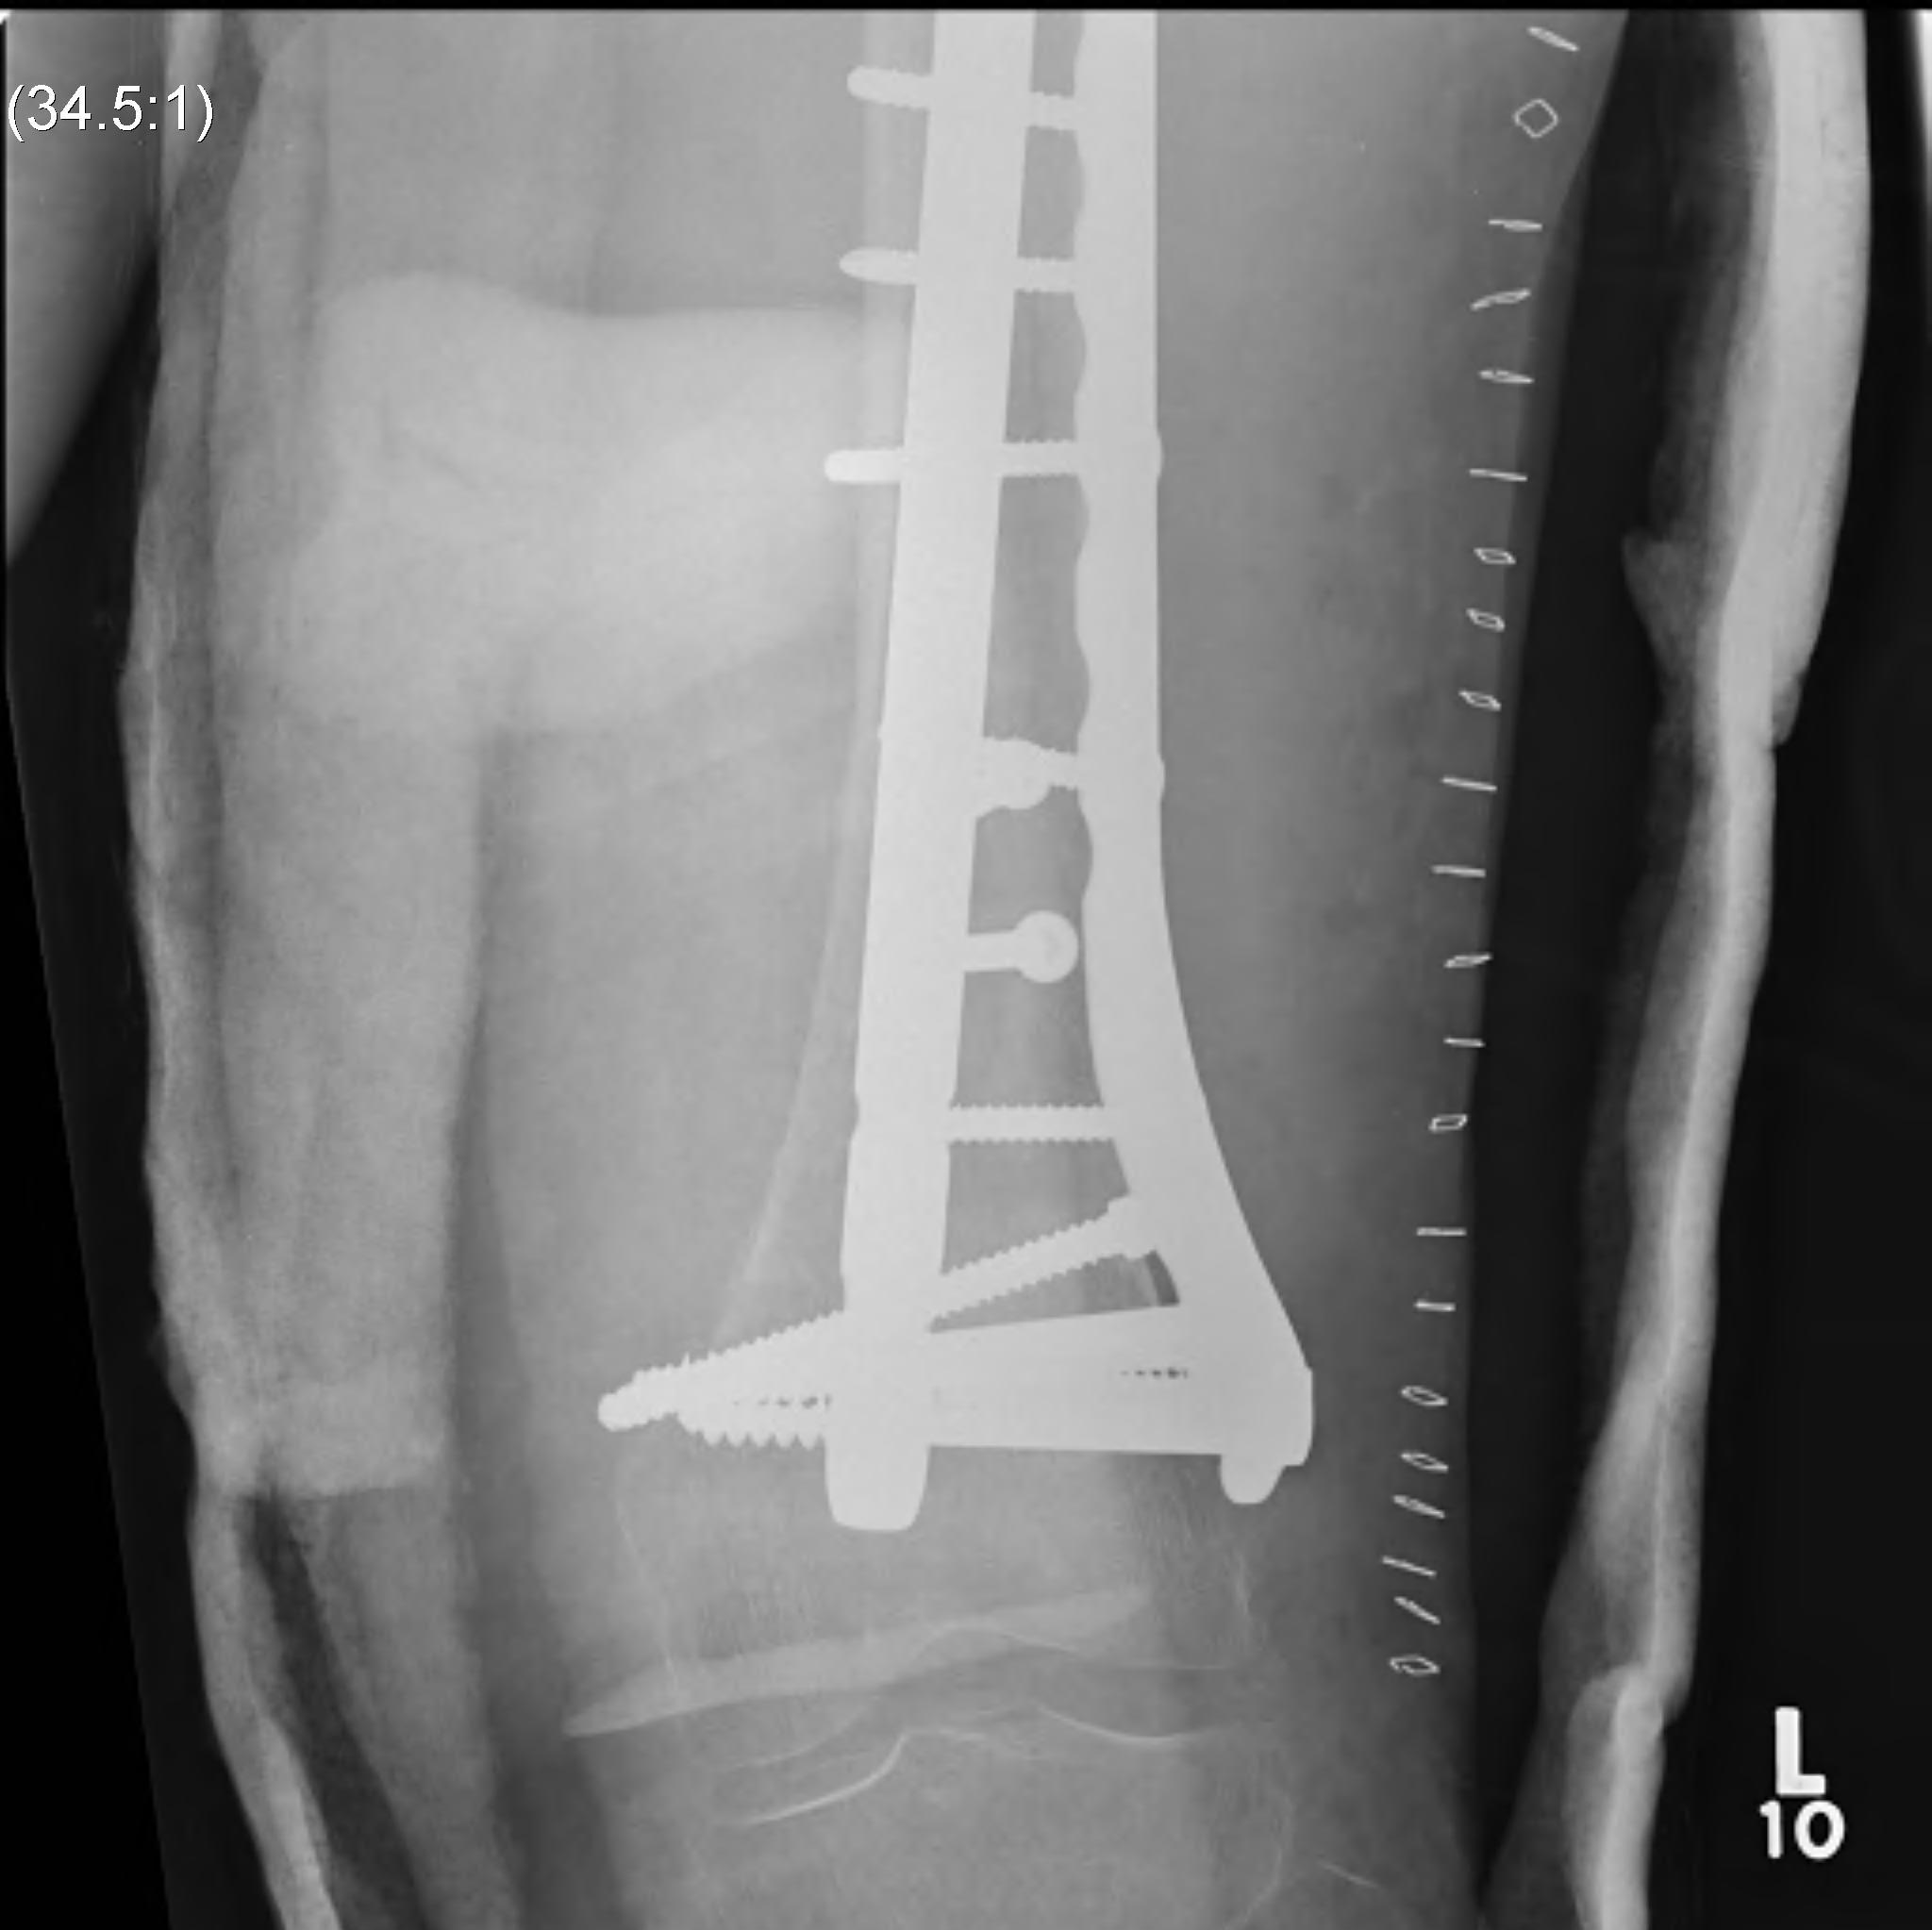

3. Femoral Plate

Indications

- associated proximal / distal femoral fracture

- vascular injury

- medulla too narrow for IMN

- paediatric population

- treatment of non union

Issues

- tension side / load bearing

- significant disruption to blood supply required

- plate will break early if union not achieved

Technique

- large fragment plate

- minimum 8 cortices each side of fracture

- need periord of NWB